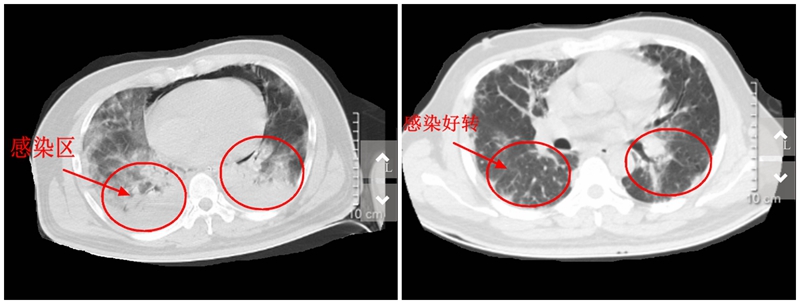

胸部CT检查竟发现小吴的肺部感染严重,被诊断为重症肺炎,住入EICU抢救。

经抗病毒、抗感染、增强免疫等治疗,病人血氧饱和度逐渐上升,一周后终于能脱离呼吸机呼吸。

【感染前后CT对比照】